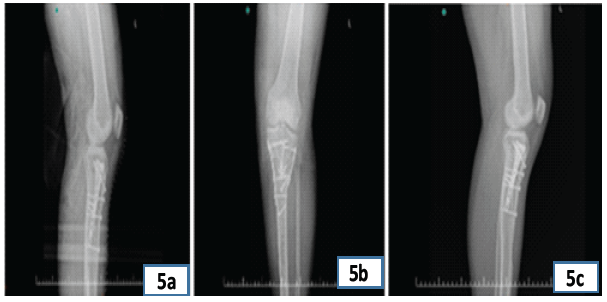

Figure 5: Postoperative radiographic images demonstrating implant position and bone healing. (a) Lateral radiograph showing fixed biplanar osteotomy with maintained alignment and implant stability; (b) Anteroposterior radiograph illustrating well-aligned knee joint and stable fixation with plates and screws; (c) Oblique radiograph highlighting bone graft incorporation and hardware position.

In Fig. 5, a retrograde intramedullary nail with interlocking screws is visible, stabilizing a femoral shaft fracture. The alignment appears maintained across all three views, showing satisfactory implant positioning.